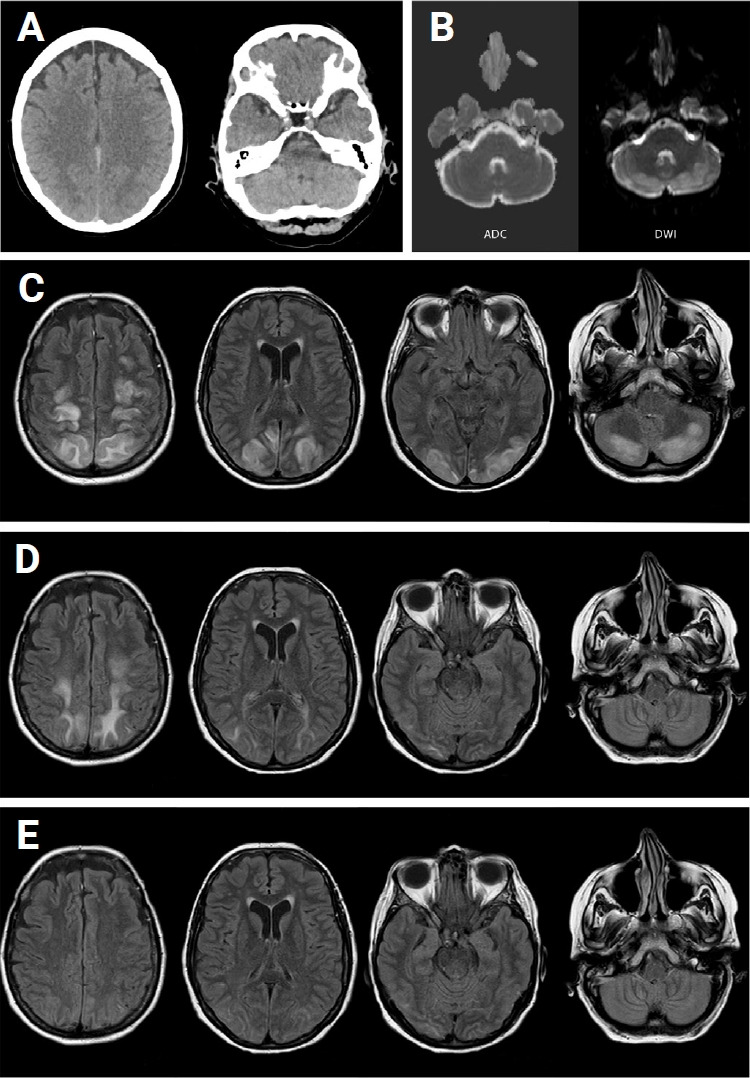

In the present case report, a 50-year-old female presented with hemiparesis and blurred vision and was subsequently diagnosed with posterior reversible encephalopathy syndrome (PRES) associated with coronavirus disease 2019 (COVID-19). Magnetic resonance imaging revealed cortico-subcortical edema with hyperintensities bilaterally in the frontoparietal and bi-occipital regions. Although PRES is a neurotoxic disorder that typically affects white matter of the brain and often is associated with hypertension, renal failure, and autoimmune disorders, recent studies have suggested that COVID-19 increases the risk of PRES. This case report presents a unique instance of COVID-19-related PRES. Unlike most previously reported cases occurring during the acute phase of severe COVID-19, our patient experienced PRES during the recovery phase with mild initial symptoms, such as fatigue and mild fever. The article discusses the pathophysiology of PRES, the potential mechanisms by which COVID-19 leads to PRES, and the treatment and outcome of the patient.